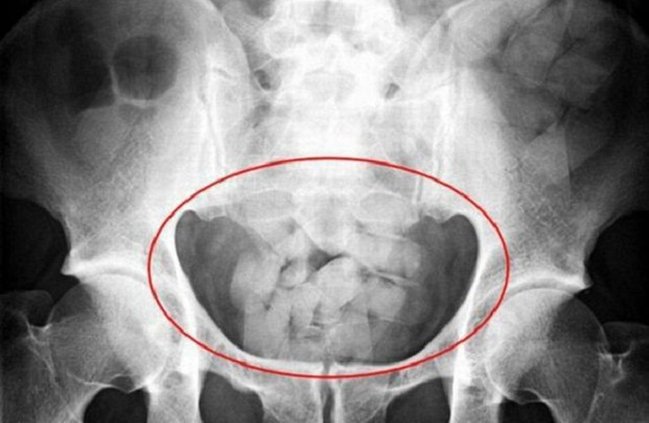

Yoxlama zamanı, vətəndaşın daxili orqanlarının tibbi müayinədən keçirilməsi zərurəti yarandığı üçün o, gömrük əməkdaşlarının müşayiəti ilə Biləsuvar Mərkəzi Rayon Xəstəxanasına aparılıb. Tibbi müayinə nəticəsində, vətəndaşın düz bağırsağından 5 ədəd bükümdə, ümumi çəkisi 170 qram olan açıq qəhvəyi rəngli narkotik vasitə-heroin və 5 ədəd "metadon" həbləri aşkar edilib.